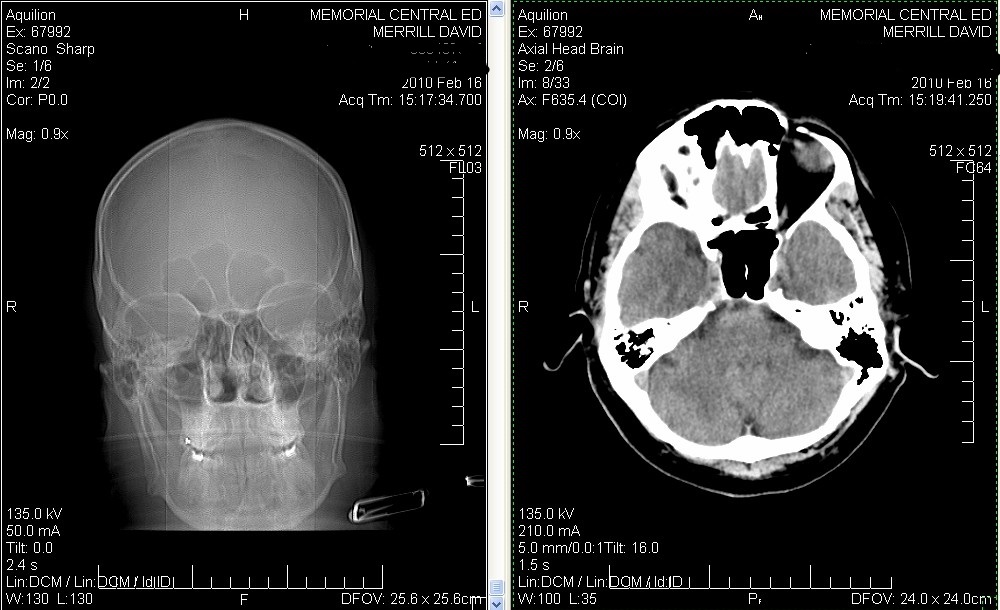

Click image for larger version

Name:	CAT Scan three stones sanitized.JPG

Views:	4

Size:	50.9 KB

ID:	42344

Really folks! Is this brain science? Look at that... If you are willing to put some humor up your nose it only costs $1!

Scanning my head topographically it becomes obvious how close the air is getting to my pineal gland, now that I have cleared out all the snot. It took about six weeks - about six years ago. And I even noticed some cottony deposits loosened up recently. Few people realize they are carrying around a low-grade sinus infection. - I suspect that some of the snot and bacteria has been up people's noses since childhood!

Name:	CAT Scan Pineal Gland.jpg

Views:	1

Size:	175.7 KB

ID:	42345